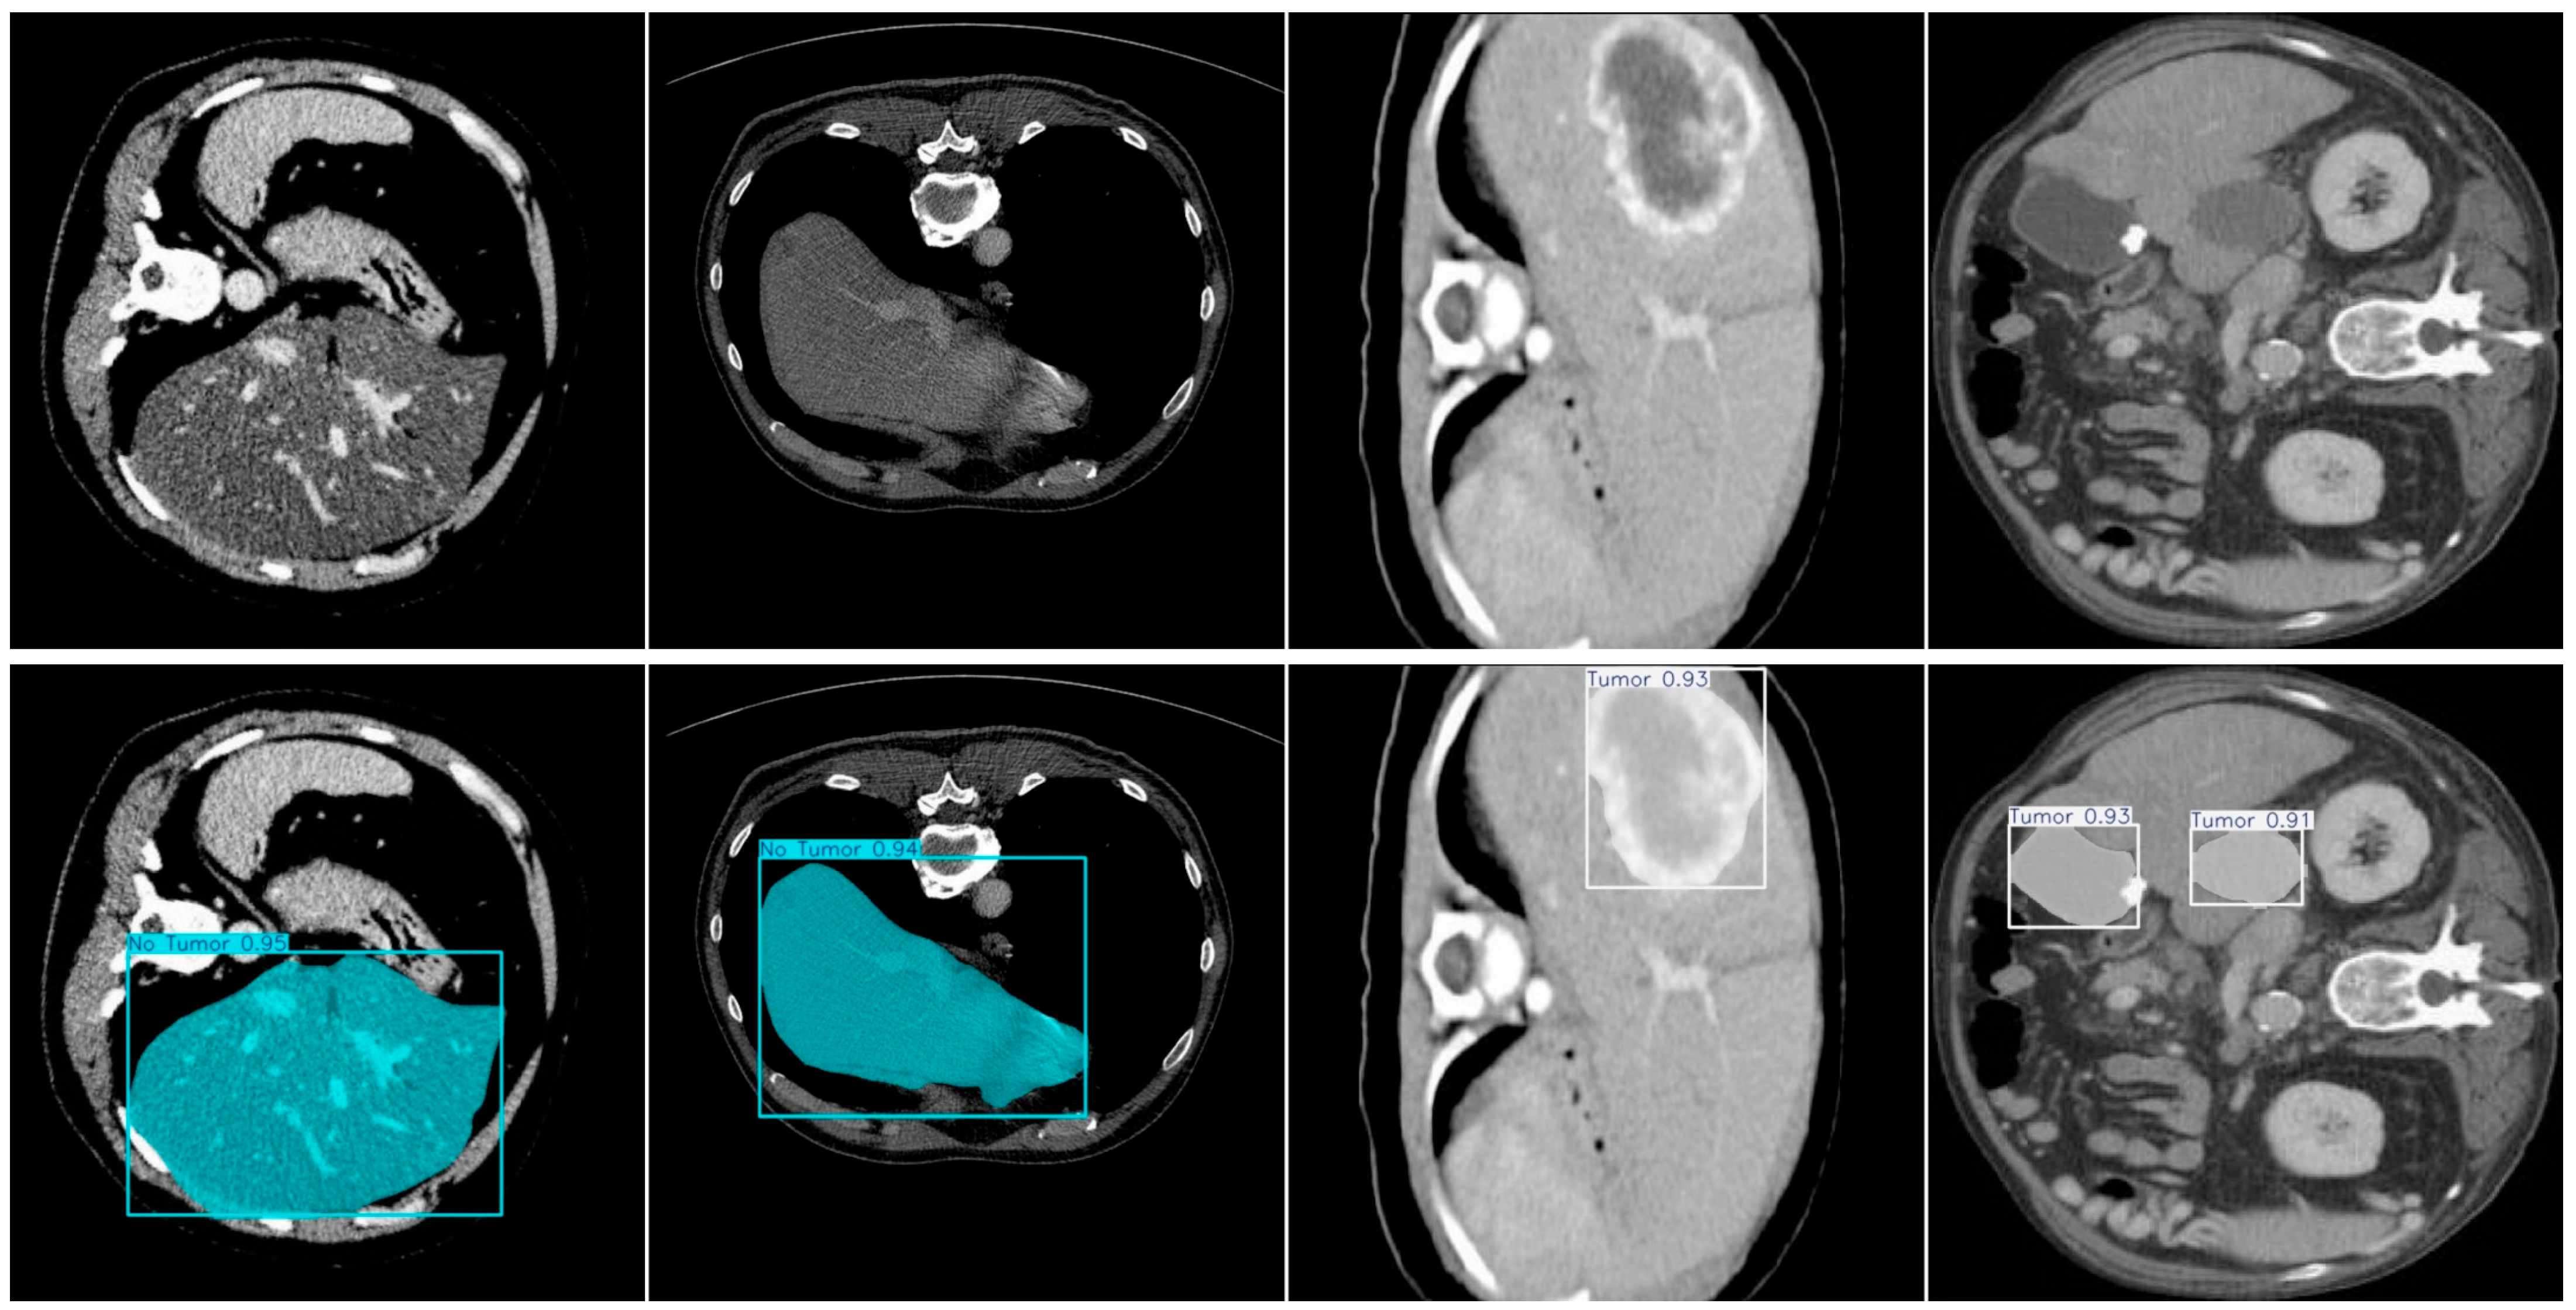

4.7. Supplementary Experiment